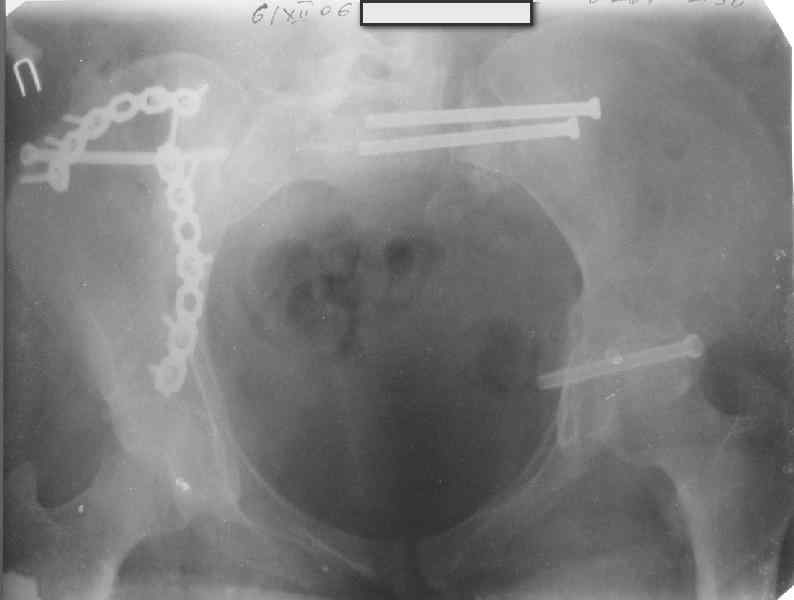

Молодая девушка 19 лет, травма 1 год назад, тогда же прооперирована.

В приложении снимки при поступлении и послеоперационные год назад.

Могу сказать одно: миграция винтов и нестабильность синтеза левого подвздошно-крестцовогоо сочленения очевидна.

Вот цитата из статьи с odoс.ru:"Идеально было бы иметь винты диаметром 7 - 8 мм с довольно широкой резьбой в 50 - 80 мм. Также необходимы более длинные винты и, в общем, наиболее часто используемые размеры - между 90 и 150 мм." Думается, в этой статье вы найдете ответы на все ваши вопросы.

Забыл добавить, что ИХМО показан реостеосинтез более длинными винтами, с более широкой резьбой, с фиксацией за правое подвдошно-крестцовое сочленение.